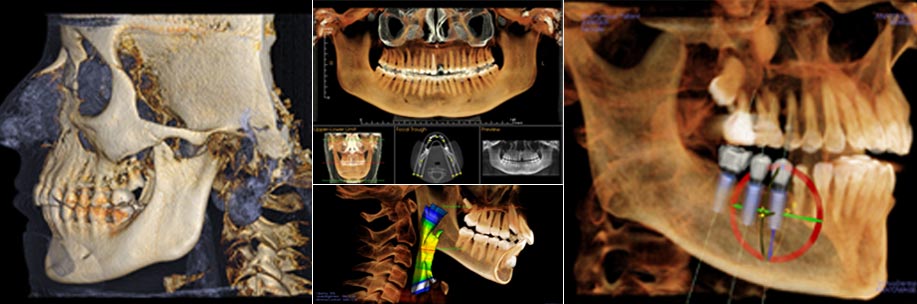

iCAT™ cone beam technology provides a 3D digital tomographic view of the patient’s area of interest. The 3D Cone Beam scanner provides nearly limitless views of the teeth while using less radiation than traditional medical CT technology. This new technology is fast, simple, and painless, providing many wonderful benefits that were unavailable only a few years ago.

While a traditional X-ray is only two-dimensional, iCAT™ technology allows Dr. Sreeni to visualize a 360-degree view of the tooth and all surrounding areas for the most comprehensive and detailed images that are then used to diagnose, plan, and complete treatment. Our 3D-guided implant technology enables us to place your implants with greater precision and accuracy than ever before, maintaining the highest quality of treatment and restoration of your smile.